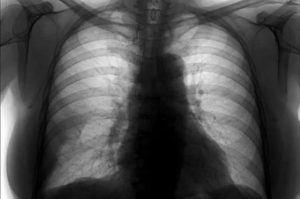

Рентген грудной клетки

- рентген грудной клетки;

Рентгенография является одним из главных методов, помогающим определить наличие различных заболеваний легких. При пневмофиброзе органы дыхания сильно видоизменяются – усиливается и деформируется легочный рисунок, увеличиваются сосудистые тени. Легочные тени со рваными краями, расположенные хаотично, говорят о последних стадиях патологии.